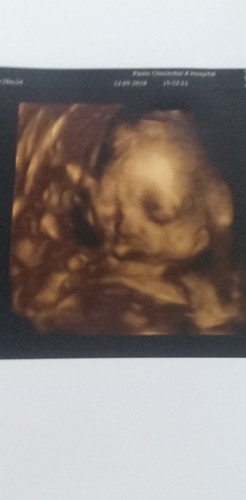

?ครั้งแรกที่เราเจอกันเบบี้ของอิแม่26สัปดาห์กับอีก3วัน?